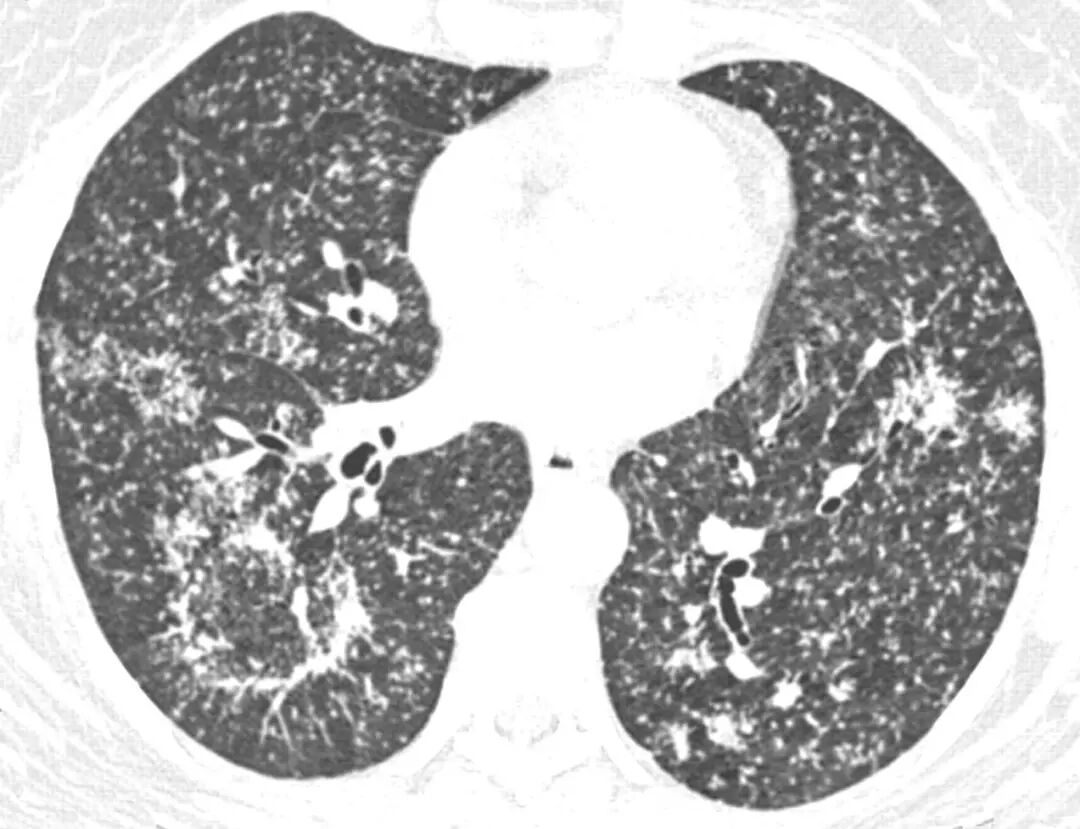

肺结核继发肺泡蛋白沉积症(PAP):

这是一个文献报道的例子,21岁小伙子干咳、低热盗汗2月,肺部影像有弥漫的磨玻璃影,但仔细看磨玻璃影里也有显著的弥漫微结节。支气管肺泡灌洗液(BALF)呈牛奶样,PAS(+)血TB抗体(+),T-SPOT(+),抗结核后6月后,肺部阴影吸收。[3]

我们将影像放大了看,和刚才所看的肺结核反晕征有一定相似性,也是由弥漫的微结节拼凑构成的。

北京协和医院田欣伦教授团队专门总结了继发性肺泡蛋白沉积症(sPAP)的特点[4],2000-2016年,北京协和医院共157例肺泡蛋白沉积症,其中只有9例(5.7%)是明确的继发性的。(sPAP的诊断:病理学确诊PAP;抗GM-CSF抗体阴性)

在sPAP的病因方面,肺结核约占一半,有4例;另外接近一半是骨髓增生异常综合征(MDS),也是4例;还有1例是慢性髓细胞性白血病(CML)。在sPAP的肺CT中,仅1/3患者有小叶间隔增厚的表现,但肺结核及MDS患者,各有一半病例有散在微结节。

前面我们回顾了结核的病理,重要特征为肉芽肿、微结节。从上述病例可知,即使临床表现有所特殊,但如果我们有目的地去看,仍然有可能找到这些微结节的蛛丝马迹,为诊断提供线索。